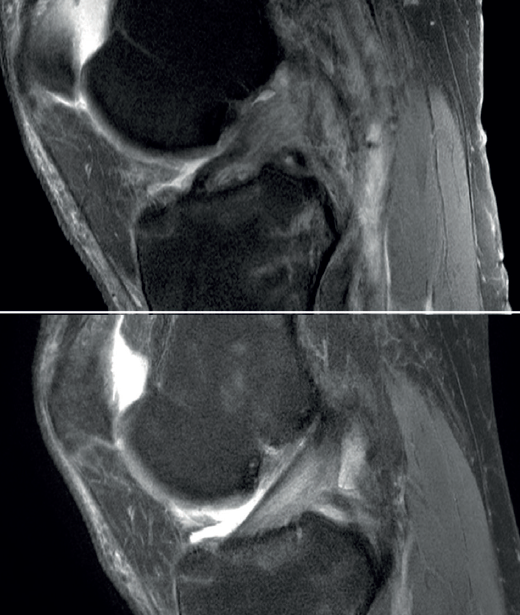

We now know from the histological study of ACL remnants after rupture that the ligament has some intrinsic capacity for spontaneous healing, as evidenced by the presence of vascular buds, nerve endings and cells with healing capacity in the remnant tissue(3). Further evidence of this self-repairing capacity can be found in the good functional results published in some patients treated on a conservative basis, especially older individuals with lesser physical demands(4)(Figure 1).

The main indication for primary ACL repair is in patients with high-grade complete or partial tears corresponding to types 1 or 2 of the original Shermanclassification(7), i.e. in avulsions of the femoral insertion (type 1) or in proximal tears leaving 75-90% of the distal ligament intact (type 2). In any case, good quality of the remaining tissue is essential. It should be noted that the incidence of tears of this kind appears to be greater in individuals over 35 years of age(7). This is not a problem, given that the incidence of re-rupture following ACL repair is higher in younger patients under 21 years of age(8,9).

With regard to the timing of surgery, the operation is ideally performed within 6 weeks of the injury(10,11,12), although good results have also been published repairing chronic tears in which the torn ACL stump heals over the posterior cruciate ligament (PCL)(13,14).